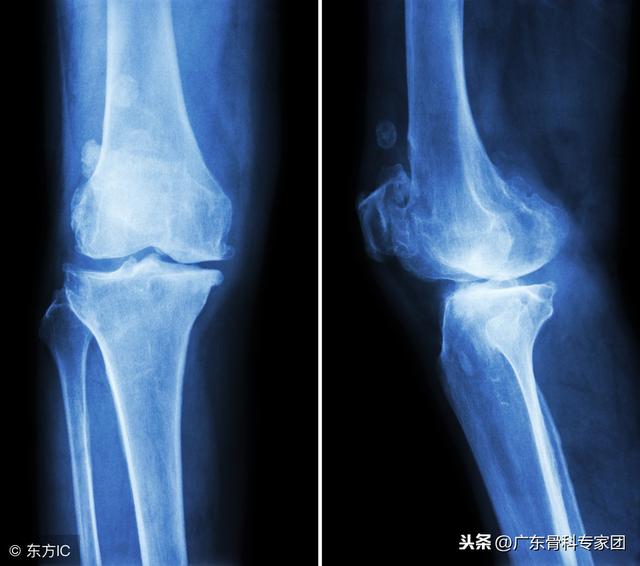

骨质增生又称骨刺,它是一种常见的骨科疾病,在老年人中发病率可以达到60%以上。很多患者一听说自己长了骨刺,顿生诸多疑问,有不少人就想当然认为需要去除而后快,其实不然。

随着年龄增长,骨头与软组织接壤处因长期承受压力、磨损等,导致骨质增生,形成骨刺。45岁以上的中老年人,尤其是女性,由于其体内激素水平下降,特别容易在颈椎、腰椎、肩、膝等关节部位的软骨退化和萎缩,长出骨刺。

骨质增生有时会让人感到关节疼痛,进而活动受限,严重影响女性的晚年生活。这个时候治疗不仅要关注骨质增生,也要从源头控制骨质疏松症,这样才能收到良好的治疗效果。

关节疼痛的根本原因在于关节内软骨的磨损,致痛因子和炎性因子产生疼痛。年轻时关节软骨很光滑,一旦外伤或者上了年纪,骨关节面磨损、不光滑了,就像磨砂玻璃一样,关节就要开始疼痛了。

骨质增生的本质是人体骨骼的一种“衰老”现象,是一种正常的生理现象。随着年龄的增长,人的脊柱和关节周围的肌肉、韧带等组织会发生退行性改变,使脊柱和关节的平衡遭到破坏,出现脊柱和关节的不稳定。

机体为了适应这些变化,恢复新的平衡状态,就会通过骨质增生的方式增加骨骼的表面积,减少骨骼单位面积上的压力,使脊柱或关节更加稳定。可以说,骨质增生现象是机体的一种自我保护机制,是机体的一种本能。

只是有时骨质增生造成了疼痛、肿胀、肢体功能障碍等症状,使人感到不舒服时,老年人才把骨质增生作为疾病来看待。所以,我们可以把膝关节的骨刺打磨掉,让关节变得光滑,减少其对膝关节半月板软骨的磨损,减轻膝关节疼痛不适的症状,比如说在膝关节镜下做微创清理术,也可以有很好的效果。